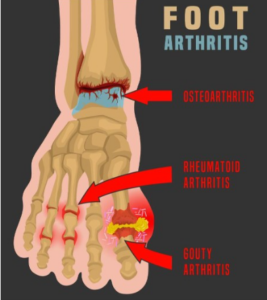

The Weight of 33 Joints: Understanding Arthritis

Arthritis is not a single disease, but a complex family of conditions. In the foot and ankle alone, there are 33 joints. When you consider the tremendous weight-bearing load these joints carry over seven or eight decades, it’s no wonder they become a primary target for inflammation.

The most common form we see is osteoarthritis, or “wear-and-tear” arthritis. As the protective cartilage  between bones erodes, you’re left with bone-on-bone friction. In Naples, I frequently treat patients for osteoarthritis of the ankle and the midfoot. They describe a dull, aching pain that is worse in the morning or after a long day of activity.

between bones erodes, you’re left with bone-on-bone friction. In Naples, I frequently treat patients for osteoarthritis of the ankle and the midfoot. They describe a dull, aching pain that is worse in the morning or after a long day of activity.

Then there is a rheumatoid arthritis (RA), an autoimmune disorder. RA is particularly aggressive because it doesn’t just cause pain; it can physically deform the foot, leading to bunions, hammertoes, and severe instability. If you notice swelling, heat, or redness in the same joints on both feet, it’s a signal that your immune system may be attacking your foundation.